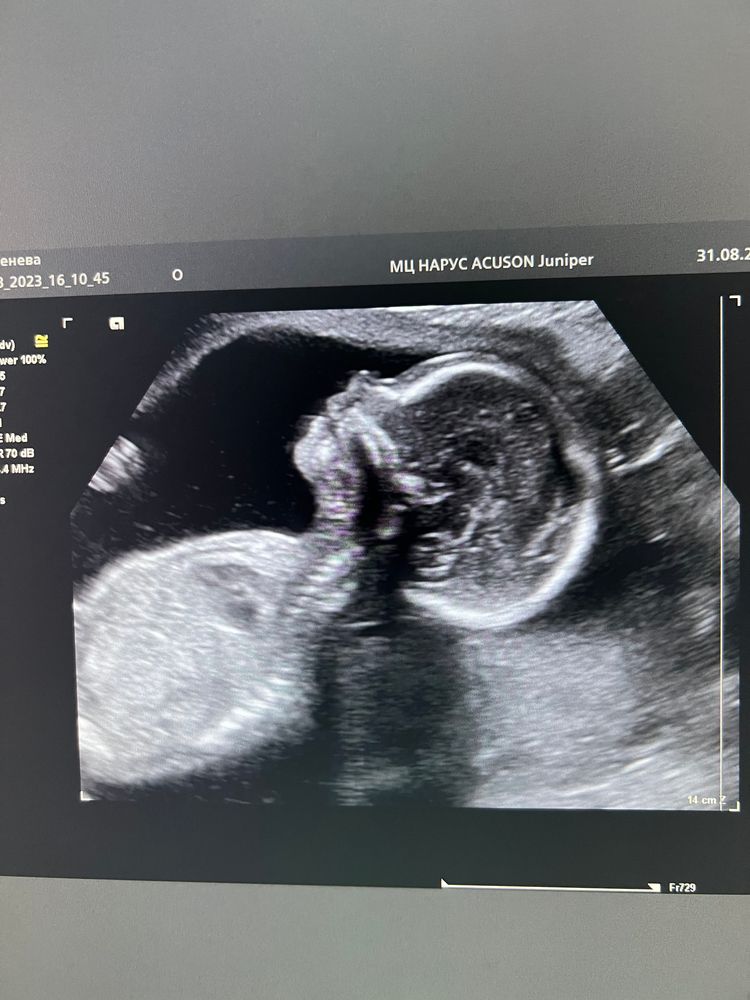

Второй скрининг

По результатам все хорошо - срокам соответствуем. Немного пугает шейка матки. На первом скрининге была 47мм, на втором 37 мм. Укорочение на 1см за 7 недель, получается. К врачу 6 сентября, посмотрим что скажет.